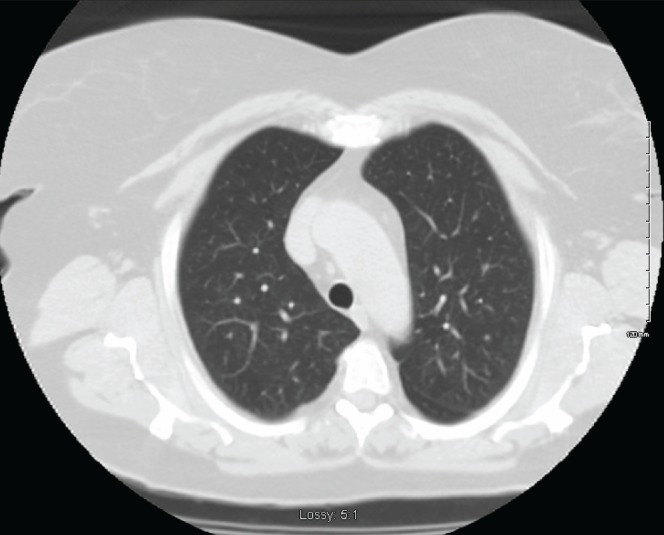

Pulmonary function assessment revealed an obstructive pattern with a forced expiratory volume in 1 s of 1.80 L (69% predicted). Stage I exercise testing revealed maximum oxygen consumption of 13.7 mL/kg/min (60% predicted). Additional work-up with thoracic computed tomography (CT) scan revealed a round 10 mm × 14 mm dominant nodule in the right middle lobe and at least 20 tiny bilateral indeterminate pulmonary nodules (Figures 1 and 2). Subsequent needle biopsy of the right middle lobe confirmed typical carcinoid tumour. Staging with positron emission CT scan revealed weak metabolic activity in the nodule with a maximum standardized uptake value of 1.80 and no metastatic disease.

Figure 1).

Bilateral lower lobe nodules with air trapping

With regard to demographics, DIPNECH is reported four times more frequently in women than in men, usually nonsmokers in the fifth or sixth decade of life (1,7). The most frequent radiographic features include mosaic air trapping and multiple small nodules (1). Bronchial wall thickening or larger carcinoid nodules may also be apparent (Figures 1 and 2).